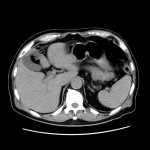

CT検査

当院では各診療科からの検査依頼があり、診断用CTが2台、放射線治療計画用CTが1台稼動しています。

CTの寝台に寝ていただき、その寝台が動きながら検査を行います。寝台がガントリー(X線発生器と検出器等から構成)と呼ばれるドーナツ状の機械を通過する際に、X線を照射し、検出しています。物質のX線の吸収差を利用して、360度方向からのデータを再構成することで輪切りの画像が完成します。空気や水などX線を吸収しにくいものは黒く、骨などX線を吸収しやすいものは白く表示されます。

また、造影剤を静脈から注射することで区別が難しかった目的の臓器や病変も見やすくなります。しかし副作用のリスクがあるためヨード過敏症の方や過去に副作用が出現した方、腎臓の機能が悪い方は主治医にお申し出ください。

当院のCT装置の最薄スライス厚は0.625mmで、これにより一つの断面だけでなくいろいろな角度からの断面を構築することや、血管や骨の3次元表示を可能にしています。また、2021年2月に導入された装置では、2種類のエネルギーを使用して撮影することで、コントラストの増強、アーチファクトの低減、さらに特定の物質を強調したり抑制した画像が作成でき、診断能の向上が見込めます。